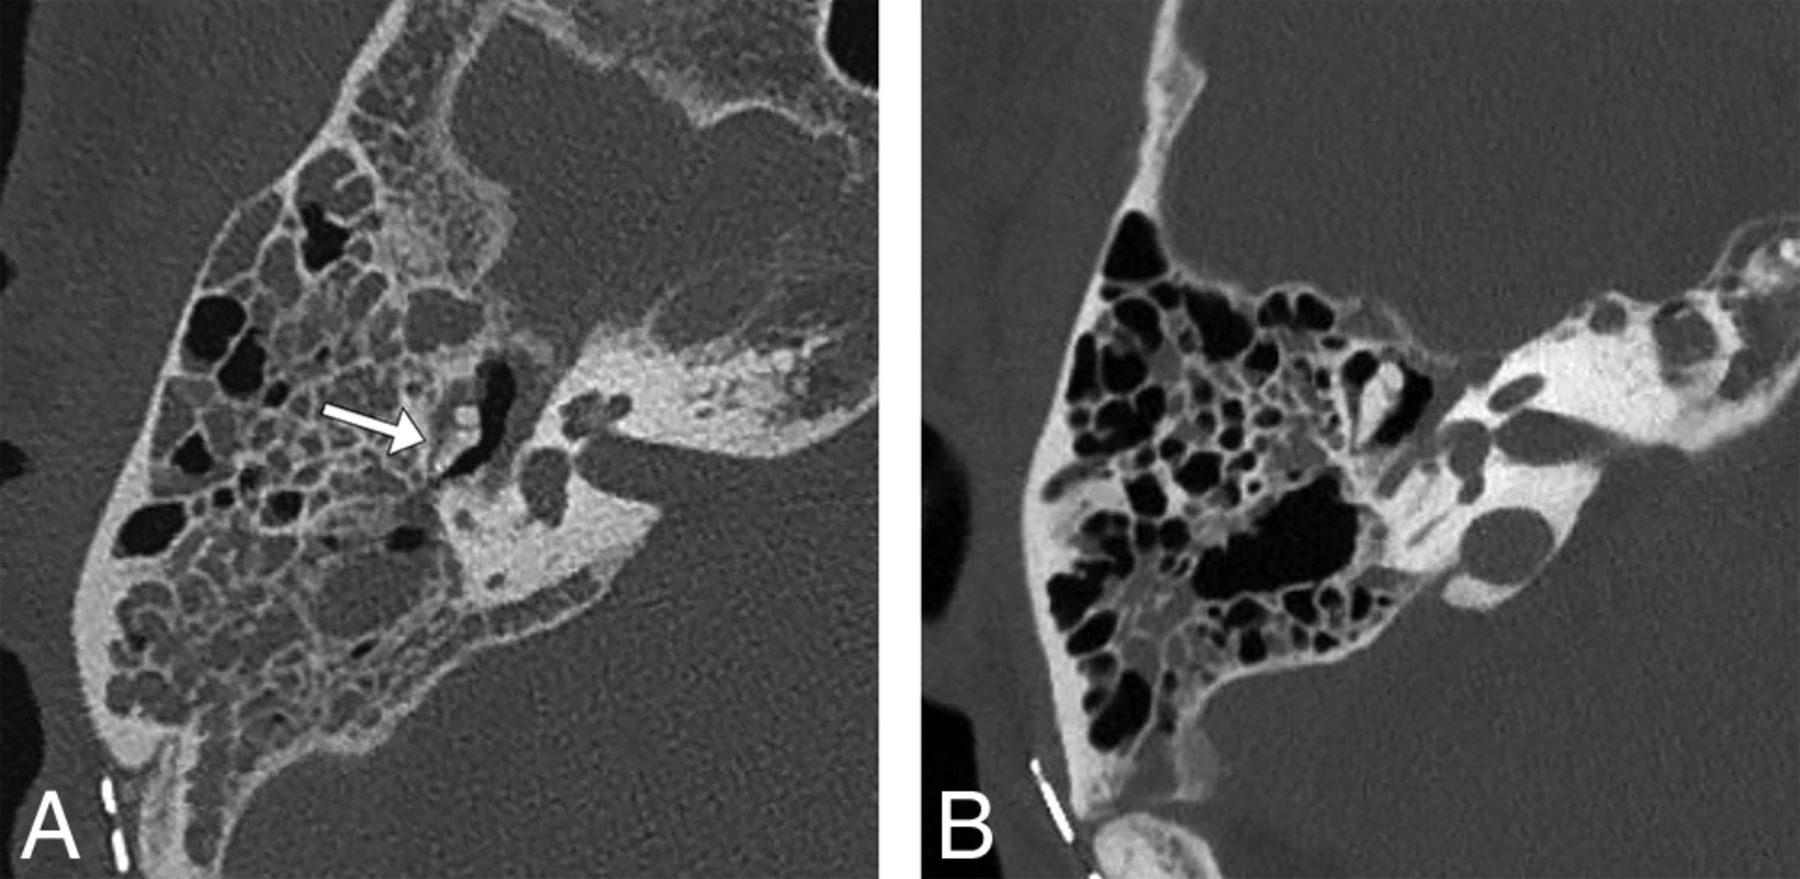

A 64-year-old man status post resection of a right vestibular schwannoma. Right temporal bone noncontrast CT images in bone windows demonstrate a possible perception error when images are reconstructed in random planes. A, Axial image in the acquisition plane obtained before the study intervention with a 29° error angle shows soft tissue in the Prussak space with a hazy appearance of the adjacent incus, suggesting possible erosion of the incus (arrow). B, Axial image in the plane of the lateral semicircular canal as reformatted by a CT technologist 3 months later following the study intervention shows the normal ice cream cone configuration of the malleus and incus with soft tissue in the Prussak space but no evident erosion of the incus, consistent with expected postoperative fluid in the middle ear cavity. The fluid had increased between the 2 examinations (not shown), so the finding is not a result of decreased fluid but a result of volume averaging with the incus body projected in an oblique plane.